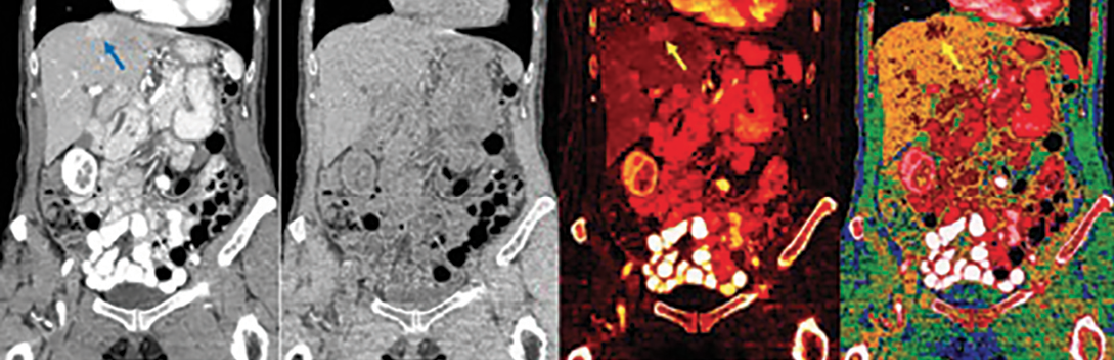

Along with substantial annual incremental improvements in scanner hardware, we occasionally see major leaps that break through prior limitations in imaging. For example, clinical CT underwent several major leaps, including the introduction of helical scanning in the early 1990s, multi-detector row scanners in the late 1990s, and multi-energy CT (MECT) in the late 2000s. This most recent advance in CT may be the most profound. MECT lets us differentiate imaged materials of similar density, such as iodine contrast agent from bone and dense tissues. MECT also provides virtual unenhanced images, iodine density maps and a host of alternate image reconstructions that can remove common ambiguities (See Figure 1). MECT technology will further evolve as energy discriminating (photon counting) CT is eventually integrated into clinical machines. Such scanners promise to improve spatial resolution, minimize radiation dose and provide an ability to see different atomic composition (colors) of materials. Much like color television ultimately supplanted black and white models, MECT will in time supplant current single energy CT imaging with far richer information than what is currently available.

Figure 1: Coronal abdominal multi-energy CT (MECT) with iodine intravenous and barium oral contrast agents. MECT scans are obtained using similar radiation dose and imaging times as conventional CT. The MECT images are routinely displayed as “conventional CT” images (left image), which simulate 120 kVp CT scans, and can also be reconstructed into multiple additional images (three right images). Virtual unenhanced images are simulations of the CT image with iodine and barium digitally subtracted. The iodine density image shows both barium and iodine as bright signal. The effective Z image shows the average apparent atomic number of the imaged atoms in each voxel. A hypervascular lesion is better seen on the iodine density image and the effective Z image than on the “conventional CT” image (arrows). Note that the barium in the bowel is not readily distinguished from the iodine in the vasculature or the solid organ parenchyma and barioum and iodine are the same color contrast agent, even in MECT image reconstructions. No second color contrast agent for MECT is currently available.